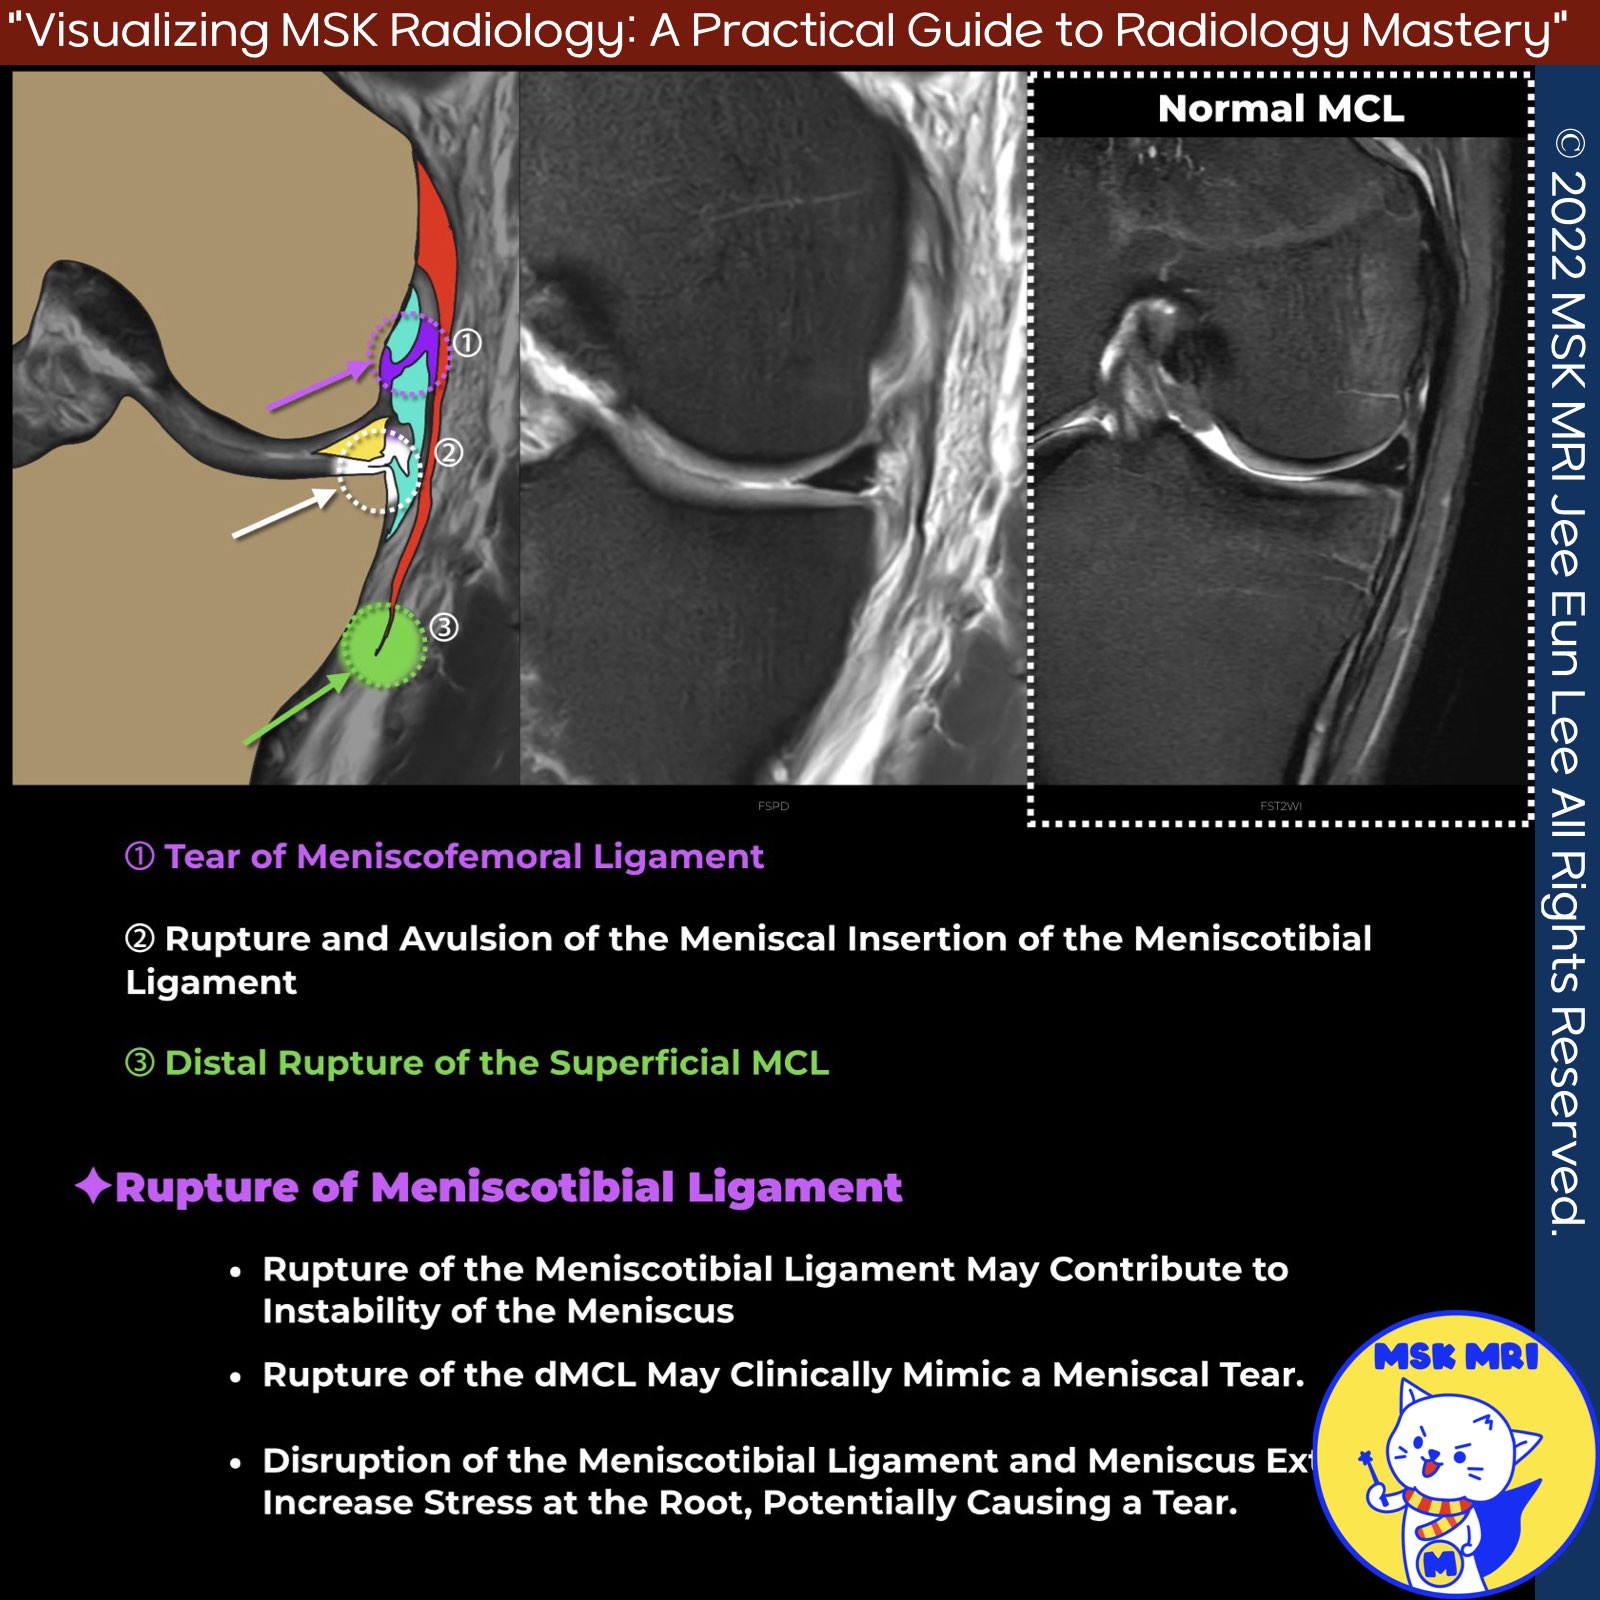

📌 Meniscotibial Ligament and Its Importance

The meniscotibial ligament plays a crucial role in maintaining the stability and position of the meniscus.

Its tibial attachment is located on the medial aspect of the medial rim of the tibial plateau, near the joint line and proximal to the attachment of the anterior arm of the semimembranosus expansion.

✅ Consequences of Meniscotibial Ligament Rupture

- Rupture of the meniscotibial ligament may contribute to instability of the meniscus, as this ligament normally adheres the meniscus tightly to the tibia and prevents extrusion.

- Disruption of the deep medial collateral ligament (dMCL) may clinically mimic a meniscal tear, highlighting the importance of careful examination.

✅ Meniscus Extrusion and Root Tears

- Disruption of the meniscotibial ligament and subsequent meniscus extrusion may increase stress at the root, potentially causing a root tear.

- Emerging evidence suggests that meniscus extrusion can also cause root tears, not just the other way around.

- Serial imaging examinations have shown that meniscotibial ligament disruption and meniscus extrusion seen on MRI may precede and contribute to the development of root tears due to increased stresses at the root.

- There is growing interest in surgical reduction (centralization) of extruded menisci, along with repair of the meniscotibial ligament, to restore the normal anatomy and biomechanics of the meniscus and potentially prevent or delay the progression of meniscal tears.